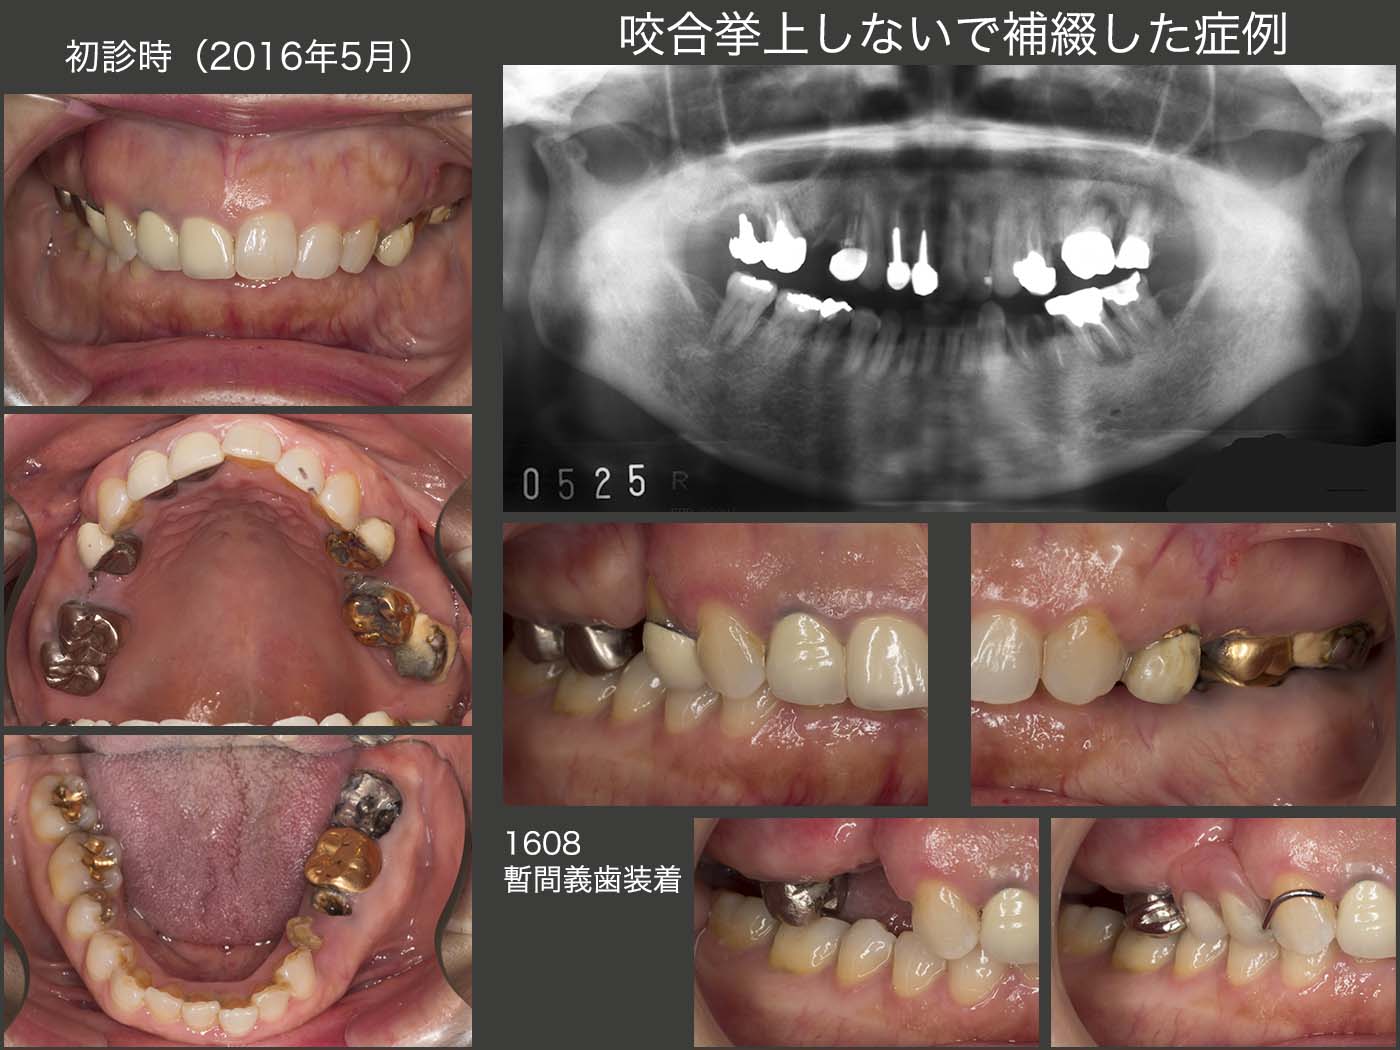

18.咬合挙上しないで補綴した症例

2016年5月初診,67歳女性.主訴は,左下の歯が取れたので治して欲しい.悪いところは治して欲しいが,予算のことも相談したい.歯医者が怖くて,治療に来るのが嫌だったとのこと.

口腔内およびパノラマX線写真をみて,治療方針をどうするか悩んだ.歯周ポケットは,左上6に最大6mm,左下6に最大5mm認められたが,その他は問題なかった.簡単な歯周治療後,まず右上の即時義歯を製作し,歯根破折している右上4および残根状態になっている右上7の抜去と同時に装着した.

上下顎前歯が咬合しているので,咬合高径を挙げる処置を行ってはいけない.しかし左側に,補綴するスペースが存在しない.また,残根状の左下4,5を保存できるかどうか迷った.